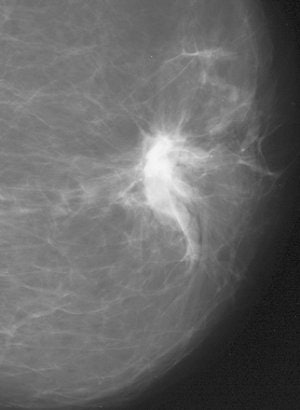

| False-negative case for all reviewers: 76-year-old woman with invasive ductal carcinoma. Above, craniocaudal mammogram obtained four years before study in which mass (arrow) was excised and was found to be benign (fibrocystic changes without atypia) at histology. Middle, screening mammogram, craniocaudal view, two years before study shows postsurgical changes. Below, screening mammogram, craniocaudal view, at time of study in which increase in density at biopsy site was not detected by any of reviewers, although area was marked by CAD system. |